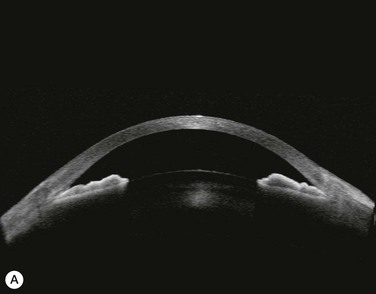

Substantial increases in anterior chamber depth and angle width following cataract extraction with intraocular lens (IOL) implantation have been demonstrated in eyes with PAC (Fig. 108-2A,B).23–25 The narrower the preoperative anterior chamber angle, the greater the alteration of angle configuration. Whereas iridolenticular contact was observed in a phakic eye, there was no iris and IOL contact in a pseudophakic one (Fig. 108-2A,B). The iris plane shifted backward, deepening the central anterior chamber by approximately 850 µm. Preoperative biometry performed in a series of 52 eyes of 48 consecutive Thai middle-aged patients who had developed acute PAC within 6 months showed that average natural lens thickness and central anterior chamber depth were 4.83 mm and 1.8 mm, respectively.26 Since the IOL (PMMA, silicone, acrylic) thickness in the 20–25 D power ranges from 0.75 mm to 1.42 mm. Replacement of the natural lens with the IOL provided up to 4 mm more axial distance within the anterior segment eliminating angle crowding and appositional closure. In addition, anterior chamber deepening with a viscoelastic during IOL implantation might break recent PAS.

Several studies have shown that extracapsular cataract extraction (ECCE) with IOL implantation is effective in opening the angle and controlling IOP in refractory PAC.27–30 Currently, ECCE has been replaced by phacoemulsification which offers a higher surgical success rate, less postoperative inflammation and fewer complications. In addition, the clear corneal approach spares the superior conjunctiva for possible filtering surgery, if needed. Phacoemulsification and IOL implantation has been reported to be highly effective in patients with uncontrolled PAC.31,32 However, up to 32% of the patients still had persistent PAS and required long-term treatment with glaucoma medication following lens removal either by ECCE or phacoemulsification and IOL implantation alone (Fig. 108-2A).5,32 Goniosynechialysis is the next step to eliminate the remaining synechiae and control the IOP (Fig. 108-2C).

Patients are treated with antiglaucoma medications and frequent topical steroids. When the inflammation subsides, the medications are then slowly tapered off within a month. Occasionally, a release of aqueous through the paracenteses at the slit lamp may be performed if a high IOP rise occurs. Gonioscopy typically reveals opening of the angle structures with irregular pigmentation on the newly exposed trabecular meshwork and the angle wall (Fig. 108-6). Angle recession or a cyclodialysis cleft are undesirable findings. If successful, anterior segment optical coherence tomography or ultrasound biomicroscopy should demonstrate separation of the PAS and reopening more than half of the entire angle (Figs 108-2, 108-7).